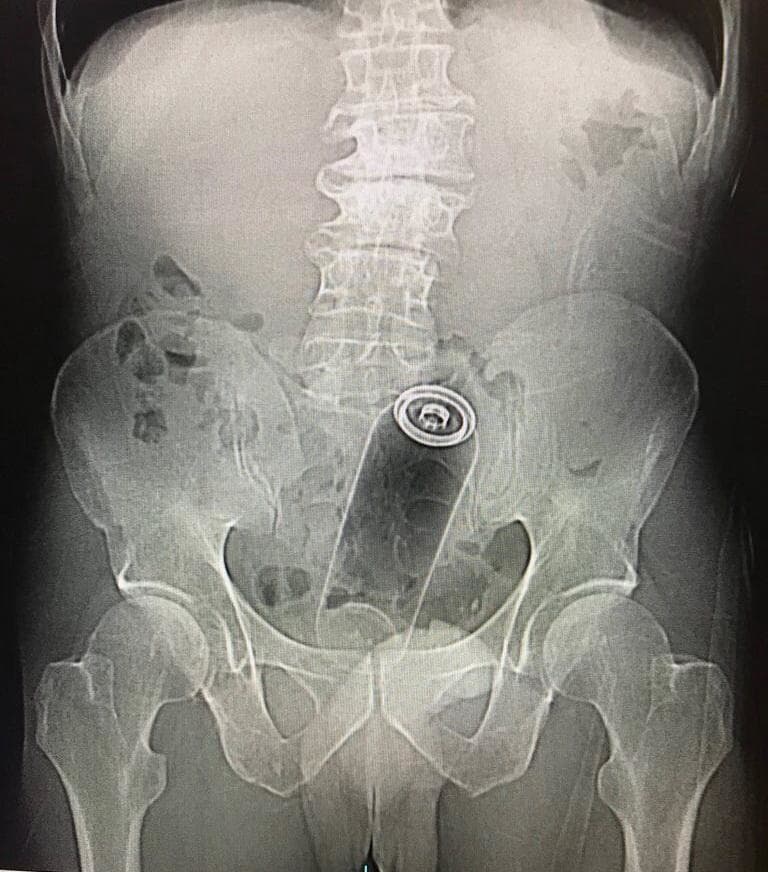

(※ TOP画は完全にイメージ)ですが、ロシアにて、大物男性タレントが、若い男2人と家飲み中に ”直腸出血” で死亡、その原因がよく分かるX線写真が話題になっています。大物男性タレントの画像+問題のX線写真…。[6]images

※ 問題のX線写真…(”直腸出血” の原因/アナルに挿入した異物)